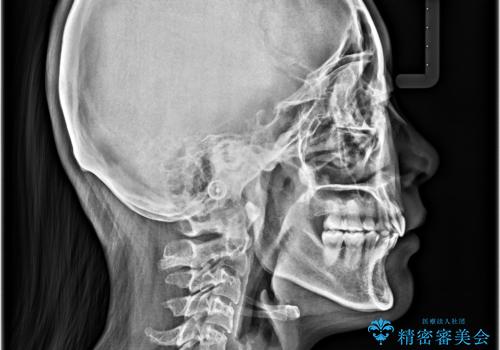

全顎的なデコボコと口元の突出感 ワイヤー装置での抜歯矯正で整った口元に

- 奥歯も含めて全体的なデコボコと前歯の突出感を気にして来院された患者様です。

上下左右第一小臼歯4本を抜歯し、ワイヤー装置にて矯正治療を行うこととしました。

想像以上に咬合力が強く、抜歯したスペースを閉じきるまでに長期間を要することとなりました。

前歯の突出感がなくなり、仕上がりには大変満足していただけました。